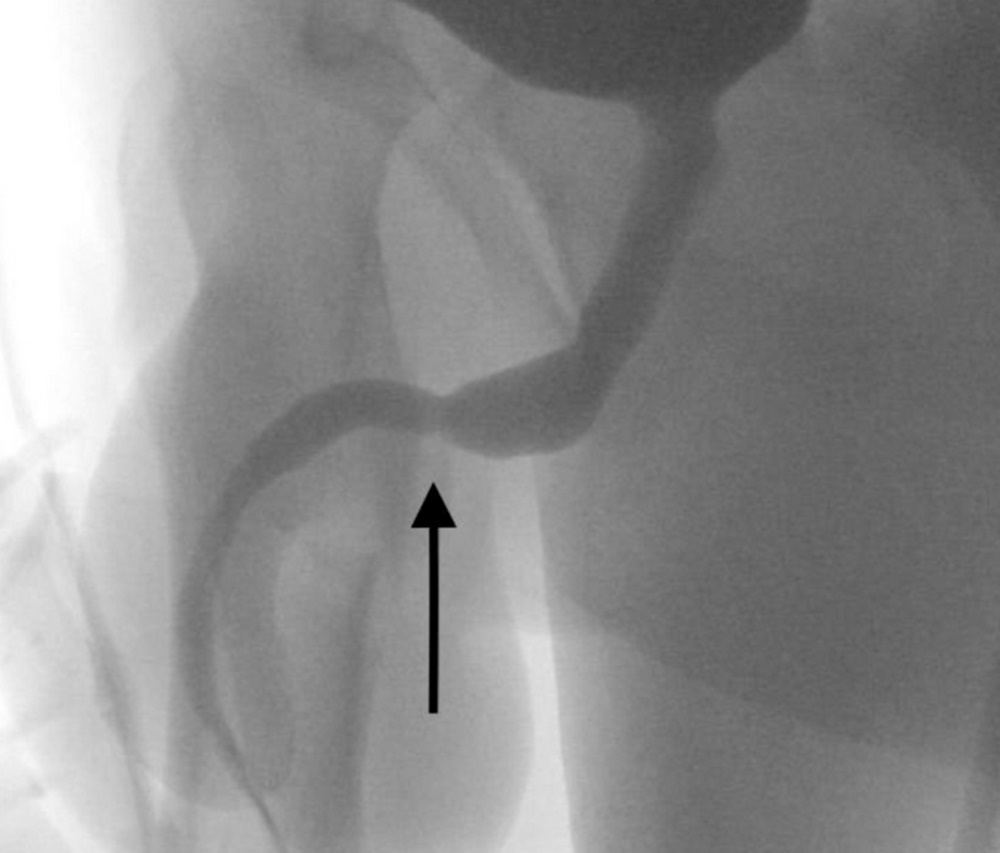

Foto: Urology Case Reports

Foto: Urology Case Reports

Foto: Urology Case Reports

Foto: Urology Case Reports